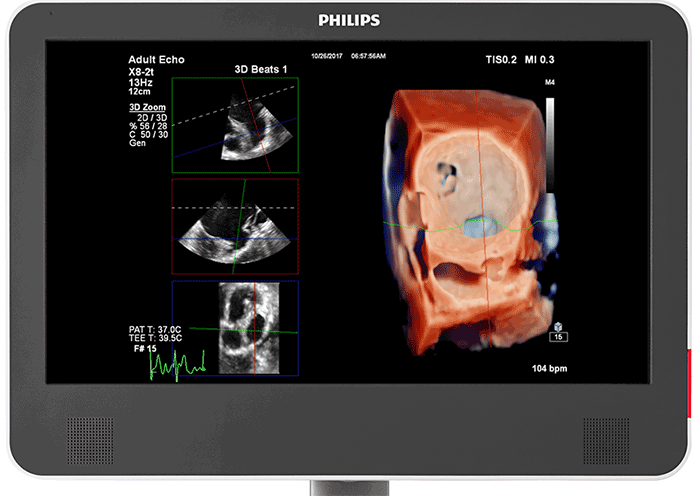

情報を豊富に含む画像 EPIQ CVx Transcend に搭載された MultiVue を使用して、インターベンション手技中に、ワンクリックで Live 3D 画像のクロッピングや、心臓組織内のカテーテル位置合わせを行うことができます。つまり、適切なタイミングでの適切な画像提供や、より迅速な 3D 測定が可能になります(例:僧帽弁の修復術中にデバイスサイジングを行うなど)。新しい EPIQ CVx Transcend を見た臨床医の 94%⁴が、EPIQ MultiVue の位置合わせツールは、インターベンション手技中²に、不適切なサイズのデバイスを選択するリスクを軽減すると回答しました。

EPIQ CVx Transcend には、22 インチの第二世代有機 EL モニタが搭載されています。さらに、MaxVue による全画面表示により、画像サイズは解像度を犠牲にすることなく従来型超音波画像と比較して 38% 大きくなっています。その結果、カテーテル検査室のような明るい環境下でも、side-by-side 表示、カラーコンペア、xPlane、Live 3D、MPR 表示もよりクリアに表示されます。